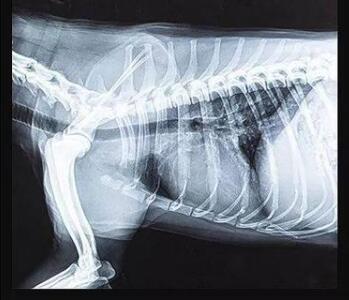

傳統(tǒng)的平板探測器,相當于普通攝像機,對于拍攝急促呼吸狀態(tài)下的寵物,成像效果存在著明顯缺陷。而新一代寵物平板探測器,宛如高速攝像機,能夠清晰記錄動物每一個精準瞬間。

寵物dr專用平板拍攝效果